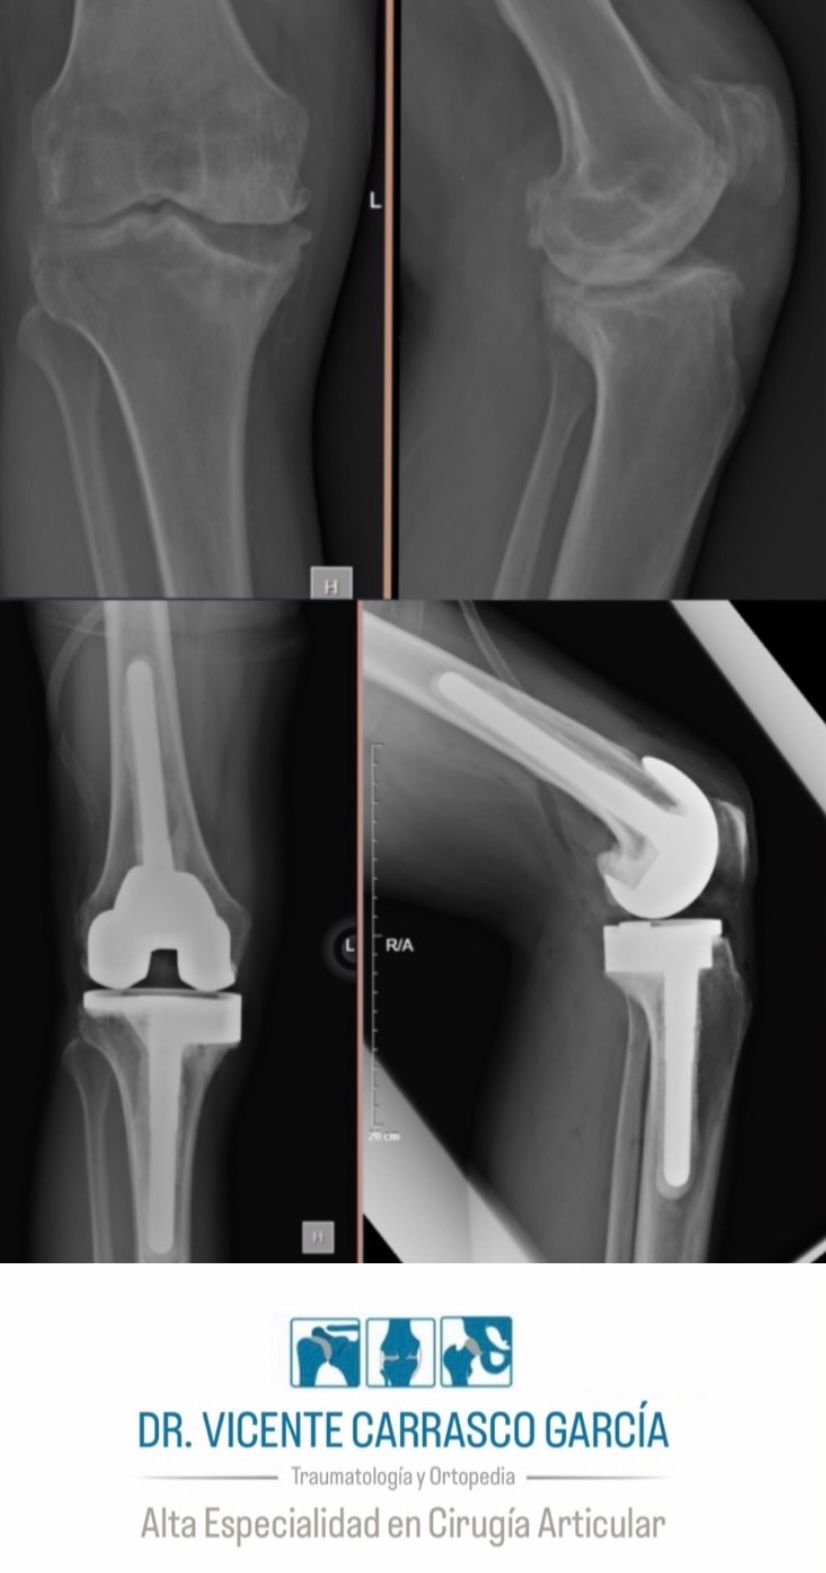

En el último año, he realizado con éxito más de 100 prótesis de rodilla y 100 prótesis de cadera, ayudando a mis pacientes a recuperar su movilidad y mejorar su calidad de vida. Mi objetivo es brindar una atención especializada y personalizada, basada en evidencia científica y en las técnicas más avanzadas disponibles en la actualidad.

• Prótesis de cadera

• Prótesis de rodilla